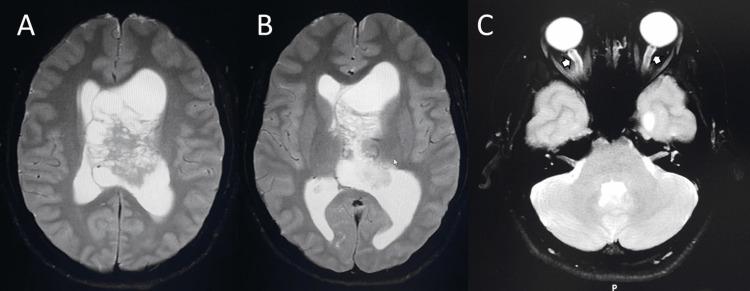

Central neurocytoma (CN) is a rare intraventricular tumor. The common presenting symptoms of CN are headache, vomiting, and visual disturbance, which results from increased intracranial pressure. This report presents a case of CN with unusual clinical presentations. A 25-year-old female with CN presented with a one-day history of unilateral headache, ipsilateral periorbital pain, multifocal paresthesias, and vomiting. Magnetic resonance images showed an intraventricular mass with a soap-bubble appearance and numerous cystic areas typical for CN, causing obstructive hydrocephalus and a midline shift. After one night of rest, her headache, periorbital pain, and paresthesias disappeared. It is possible that the tumor could be mobile with regard to the patient's head position, causing occasional obstruction of the foramen of Monro. Due to the tumor size, which was larger than 4 centimeters, the surgical approach with either gross tumor resection or subtotal resection plus adjuvant radiotherapy should be carefully considered.

中枢神经细胞瘤(CN)是一种罕见的脑室内肿瘤。CN的常见症状为头痛、呕吐和视觉障碍,这些症状由颅内压升高引起。本报告介绍了一例具有不寻常临床表现的CN病例。一名患有CN的25岁女性,有一天的单侧头痛、同侧眶周疼痛、多灶性感觉异常和呕吐病史。磁共振成像显示脑室内有一个呈肥皂泡样外观且有许多典型CN囊性区域的肿块,导致梗阻性脑积水和中线移位。经过一晚休息后,她的头痛、眶周疼痛和感觉异常消失了。肿瘤可能会随着患者头部位置移动,偶尔阻塞Monro孔。鉴于肿瘤大小超过4厘米,应仔细考虑采用肿瘤全切或次全切除加辅助放疗的手术方法。